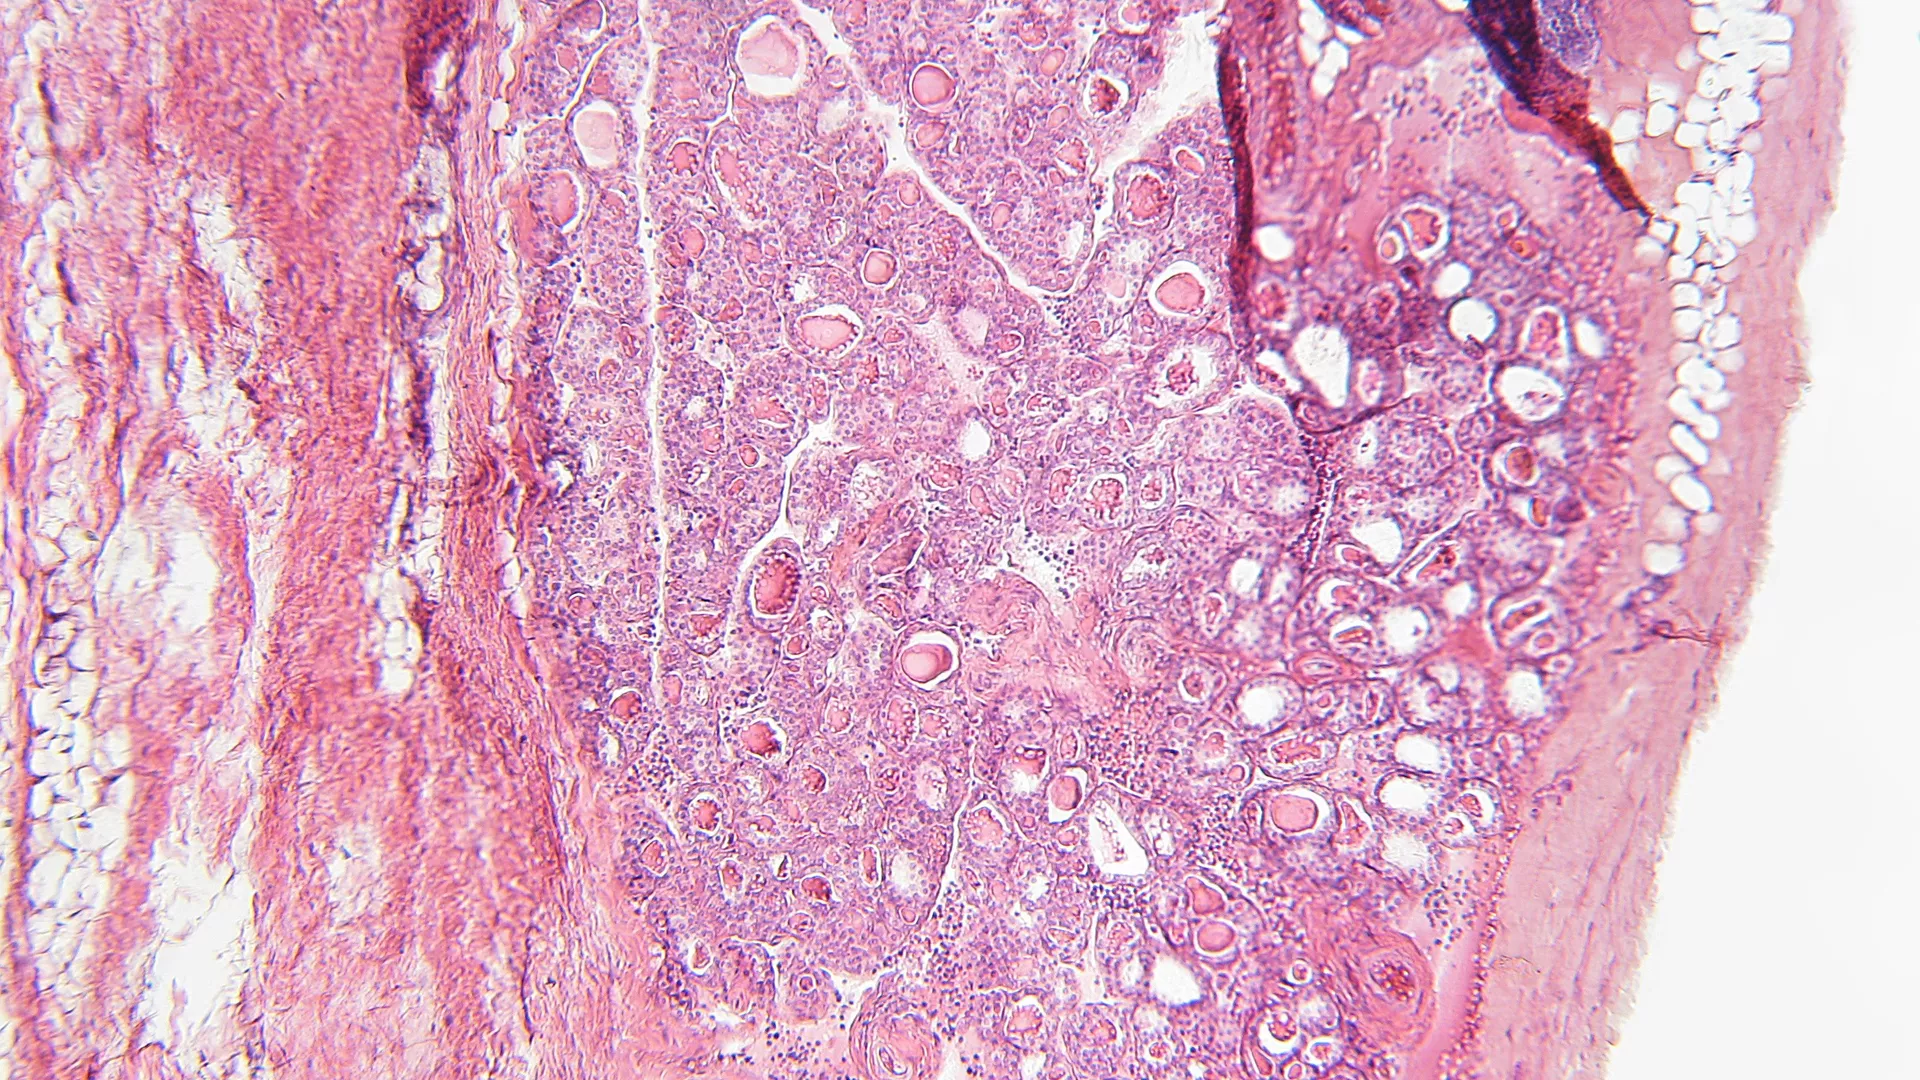

Mfsd2a is important for maintaining epidermal homeostasis.

The skin epidermis is a multilayered lipid rich organ completely reliant on exogenous delivery and uptake of the essential fatty linoleate for the synthesis of